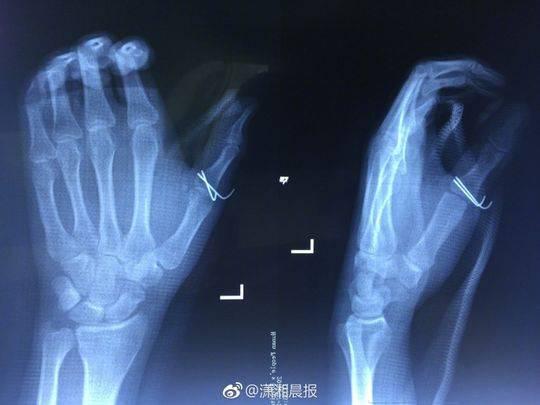

當晚10點,該院創(chuàng)傷骨病科何畔副主任醫(yī)師等為小袁施行 “ 左手清創(chuàng)探查、左拇指近節(jié)指骨骨折切開復位 + 克氏針內(nèi)固定術(shù) ”,手術(shù)歷時 2小時順利完成。術(shù)后,小袁的左手需采用石膏固定4~6周。